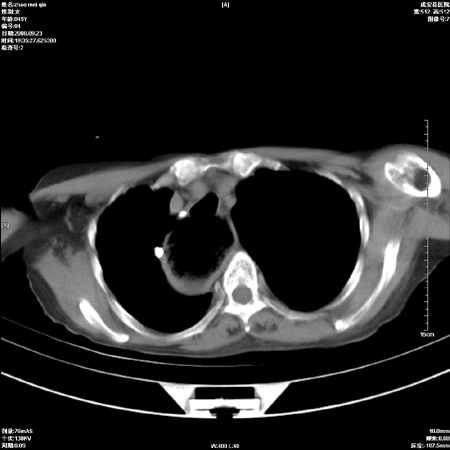

外伤后1小时 胸疼 是外伤后引起的吗?

食道扩张明显下端逐渐变窄,倒像贲门失迟缓

考虑术后改变(胸腔胃),建议询问病史.

非外伤性改变,典型的贲门失迟缓症

食道扩张明显下端逐渐变窄,大量食物存留,象贲门失迟缓症。